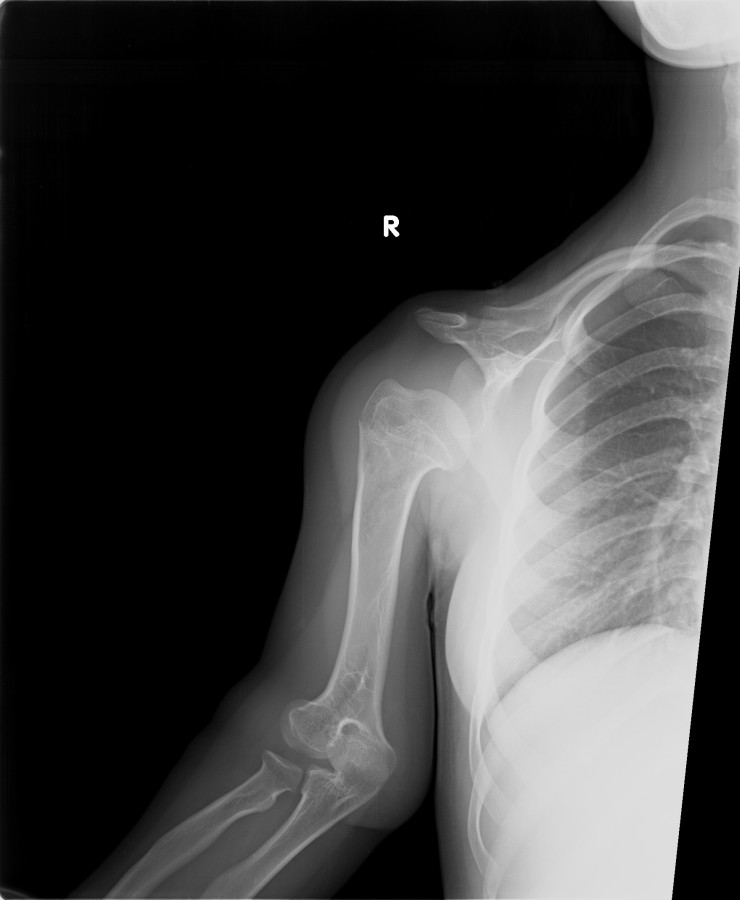

13-15 yaşlar arasında Her iki humerusu (kol) 8-12 cm boy uzatma Dirseklerin fleksiyon deformitesini düzeltme Ortalama eksternal fiksasyon tedavi süresi = 6-8 ay Alt uzuvların iki uzatması arasında üst uzuvlar uzatılarak alt uzuvların dinlenmesi sağlanmış olur. Cihaz çıkartıldıktan sonra en erken ikinci uzatmaya başlama süresi 6 aydır. Bilateral femoral uzatmalarda uzatma fazı sırasında hastanın yürümesi mümkün değildir. Ayakta durmaya sadece hasta transferi sırasında izin verilir. Uzatma fazında ambulasyona sadece tekerlekli sandalye ile izin verilir. Konsolidasyon fazında ise tedrici olarak daha fazla yük verilmesine ve cihazın çıkmasına yakın serbest yürümeye izin verilir. Bilateral tibial uzatmalarda ilk günden itibaren yürüteç veya koltuk değneği ile hastanın yük vermesine izin verilir. Uzun gezintiler tekerlekli sandalye ile yapılmalıdır. Bilateral humeral uzatmalarda hemen hemen hiçbir aktivite kısıtlaması yoktur. Uzatma süresince her iki haftada bir yapılan takiplerde kantitatif duyusal sinir testleri doktor tarafından yapılmalıdır. Bu gelişmekte olan sinir sorunlarını klinik olarak ortaya çıkmadan yakalamaya izin verir. Femoral ve humeral uzatmalarda çok nadir görülmesine rağmen tedavi edilmedikleri durumda düşük ayağa (ayağı yukarı çeken kasları innerve eden sinirin felci) neden olabilirler. Eğer erken tespit edilir ve uzatmanın hızı azaltılırsa, sinir problemi genellikle kendiliğinden düzelir ve uzatmaya düşük hızda devam edilir. Uzatmada yavaşlamaya rağmen sinir problemi devam ederse sinirin cerrahi olarak gevşetilmesi gerekir. Bu işlem 1cm’ lik bir kesi ile yapılabilen ve hastanede bir gece kalmayı gerektiren küçük bir işlemdir. Bu ameliyat el bileğinde sinir sıkışması (karpal tünel sendromu) için yapılana benzerdir.

Vaka 1